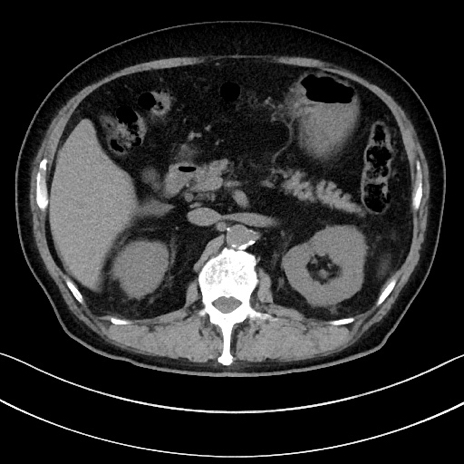

冠状断像

【症例】70歳代男性

【主訴】腹痛

【現病歴】今朝から腹痛あり。全体的に痛い。特に左上の方。排ガスが今日はない。冷や汗が出る。

【既往歴】直腸癌術後

【身体所見】左側腹部〜上腹部に圧痛あり。腹膜刺激症状明らかなではない。軽度反跳痛。左下腹部に術後瘢痕あり。

【データ】WBC 7700、CRP 0.02